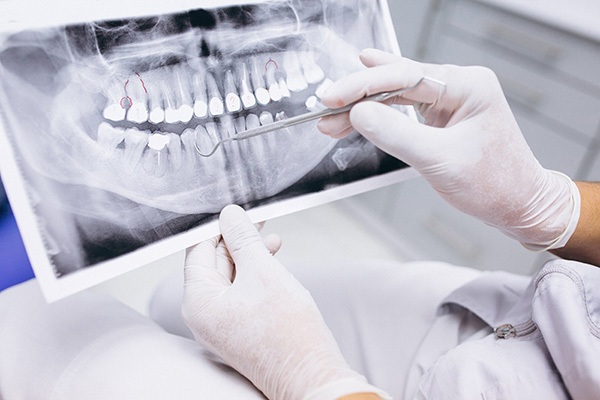

Ортопантомограмма

Панорамный двухмерный снимок всех зубов

470 рублей